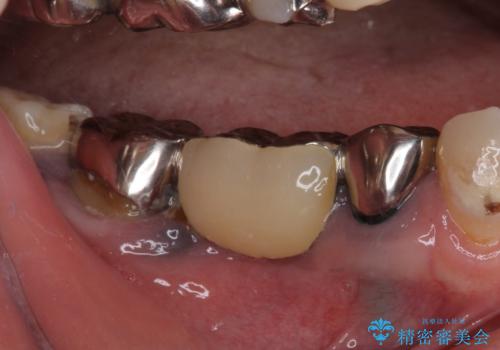

- 全顎的に銀歯が多く、その中でも目立って気になる奥歯のブリッジをセラミックに替えたいとのことで来院された患者様です。

上顎のブリッジを先に交換したものの、今度は下顎のブリッジ支台歯が食事もできないほど痛み出したとのことでした。

銀歯の適合が悪く、土台の歯に虫歯多く残っていたので、痛む歯の根管治療とファイバーコアによる土台植立を行い、フルジルコニア製ブリッジを装着することとしました。